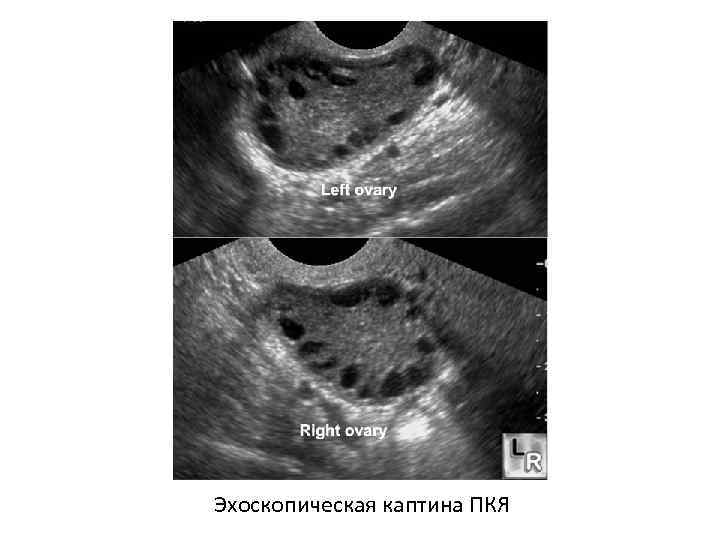

Диагностика • Эхоскопические критерии ПКЯ: – ↑ яичников > 9 см 3; – ↑ площади гиперэхогенной стромы (>0, 34 – патогномоничное соотношение стромы к площади фолликулов); – кистозно атрезирующие фолликулы размером 5 8 мм не менее 10 (критерий Адамса); – усиленный кровоток и обильная сосудистая сеть при допплерометрии.

Эхоскопическая каптина ПКЯ